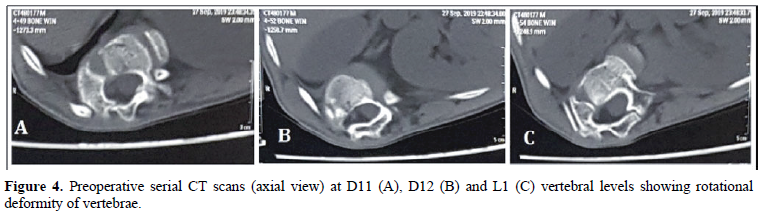

A 14 years old male child presented to the department of Orthopedics, King Edward Memorial Hospital, Mumbai in September 2019, with severe deformity of his spine (Figure 1). He also complained of difficulty in standing and walking along with severe backache. Investigations revealed a D12 hemivertebra with resultant gross kyphoscoliotic deformity compressing the spinal cord (Figures 2 - 9). The child was treated by an 11 hour long corrective surgery, during which continuous neuro-monitoring was done (Figures 10A – H). He underwent resection of the D12 hemivertebra and insertion of a titanium cage with bone graft. The kyphoscoliotic deformity was corrected following vertebral column resection & posterior instrumentation with pedicular screws and rods (Figure 11). He had an uneventful operative and postoperative course. He was given physiotherapy in the form of gait training & trunk stabilization exercises with full weight bearing. He was given a whole body contact brace at discharge on postoperative day16. The patient reported improvement of weakness in both the lower limbs along with an excellent cosmetic outcome (Figures 12 & 13). This surgery was carried out free of cost under ‘Pradhan Mantri Jan Arogya Yojana (PMJAY)’ scheme.